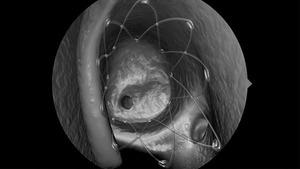

Intersect, is the only company that has developed drug releasing bio-absorbable implants (drug eluting sinus stents- DESS) that enable targeted and sustained release of therapeutic agents, increasing the effectiveness of the sinus surgery.

The US DESS market is expected to increase at a significant growth rate during the forecasted period (2016-2021). The US DESS market is supported by various growth drivers, such as limitations of FESS treatment, benefits of DESS, increasing per capita healthcare expenditure, cost effectiveness of DESS, etc. Yet, the market faces certain challenges, such as, reimbursement issues, dependability on individual physicians experience, limited trials after BSD, etc.